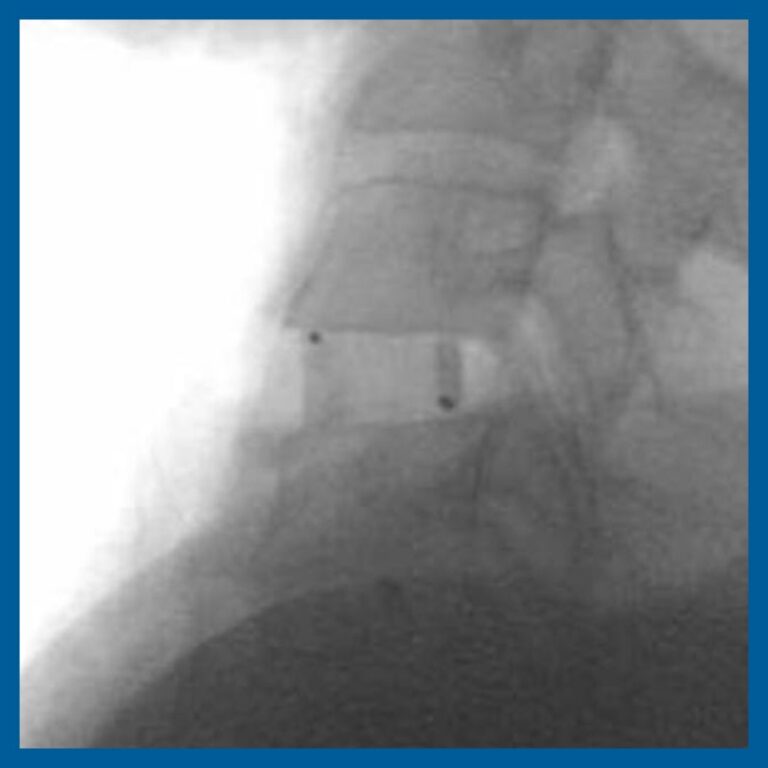

Radiolucent and Radiovisible

INTEGRATE® is both radiolucent and radiovisible for superior post-operative imaging.

The device is available in a variety of footprints, lordosis and heights to accommodate variations in the individual pathology and anatomy of the patient. The superior and inferior surfaces of the device contain a pattern of teeth to provide for initial stability. Radiopaque markers are placed in the device to aid in determining the location of the implant intra- and post-operatively.

- Tantalum markers for radiographic visualization

- Radiolucent for post-operative assessment of fusion